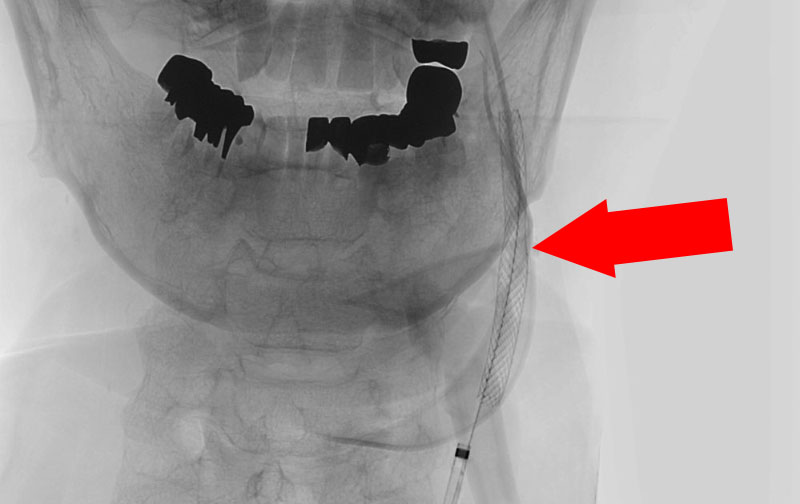

1222

'22年4月26日

左内頚動脈狭窄症

70代

院内外来

手術写真

治療

前